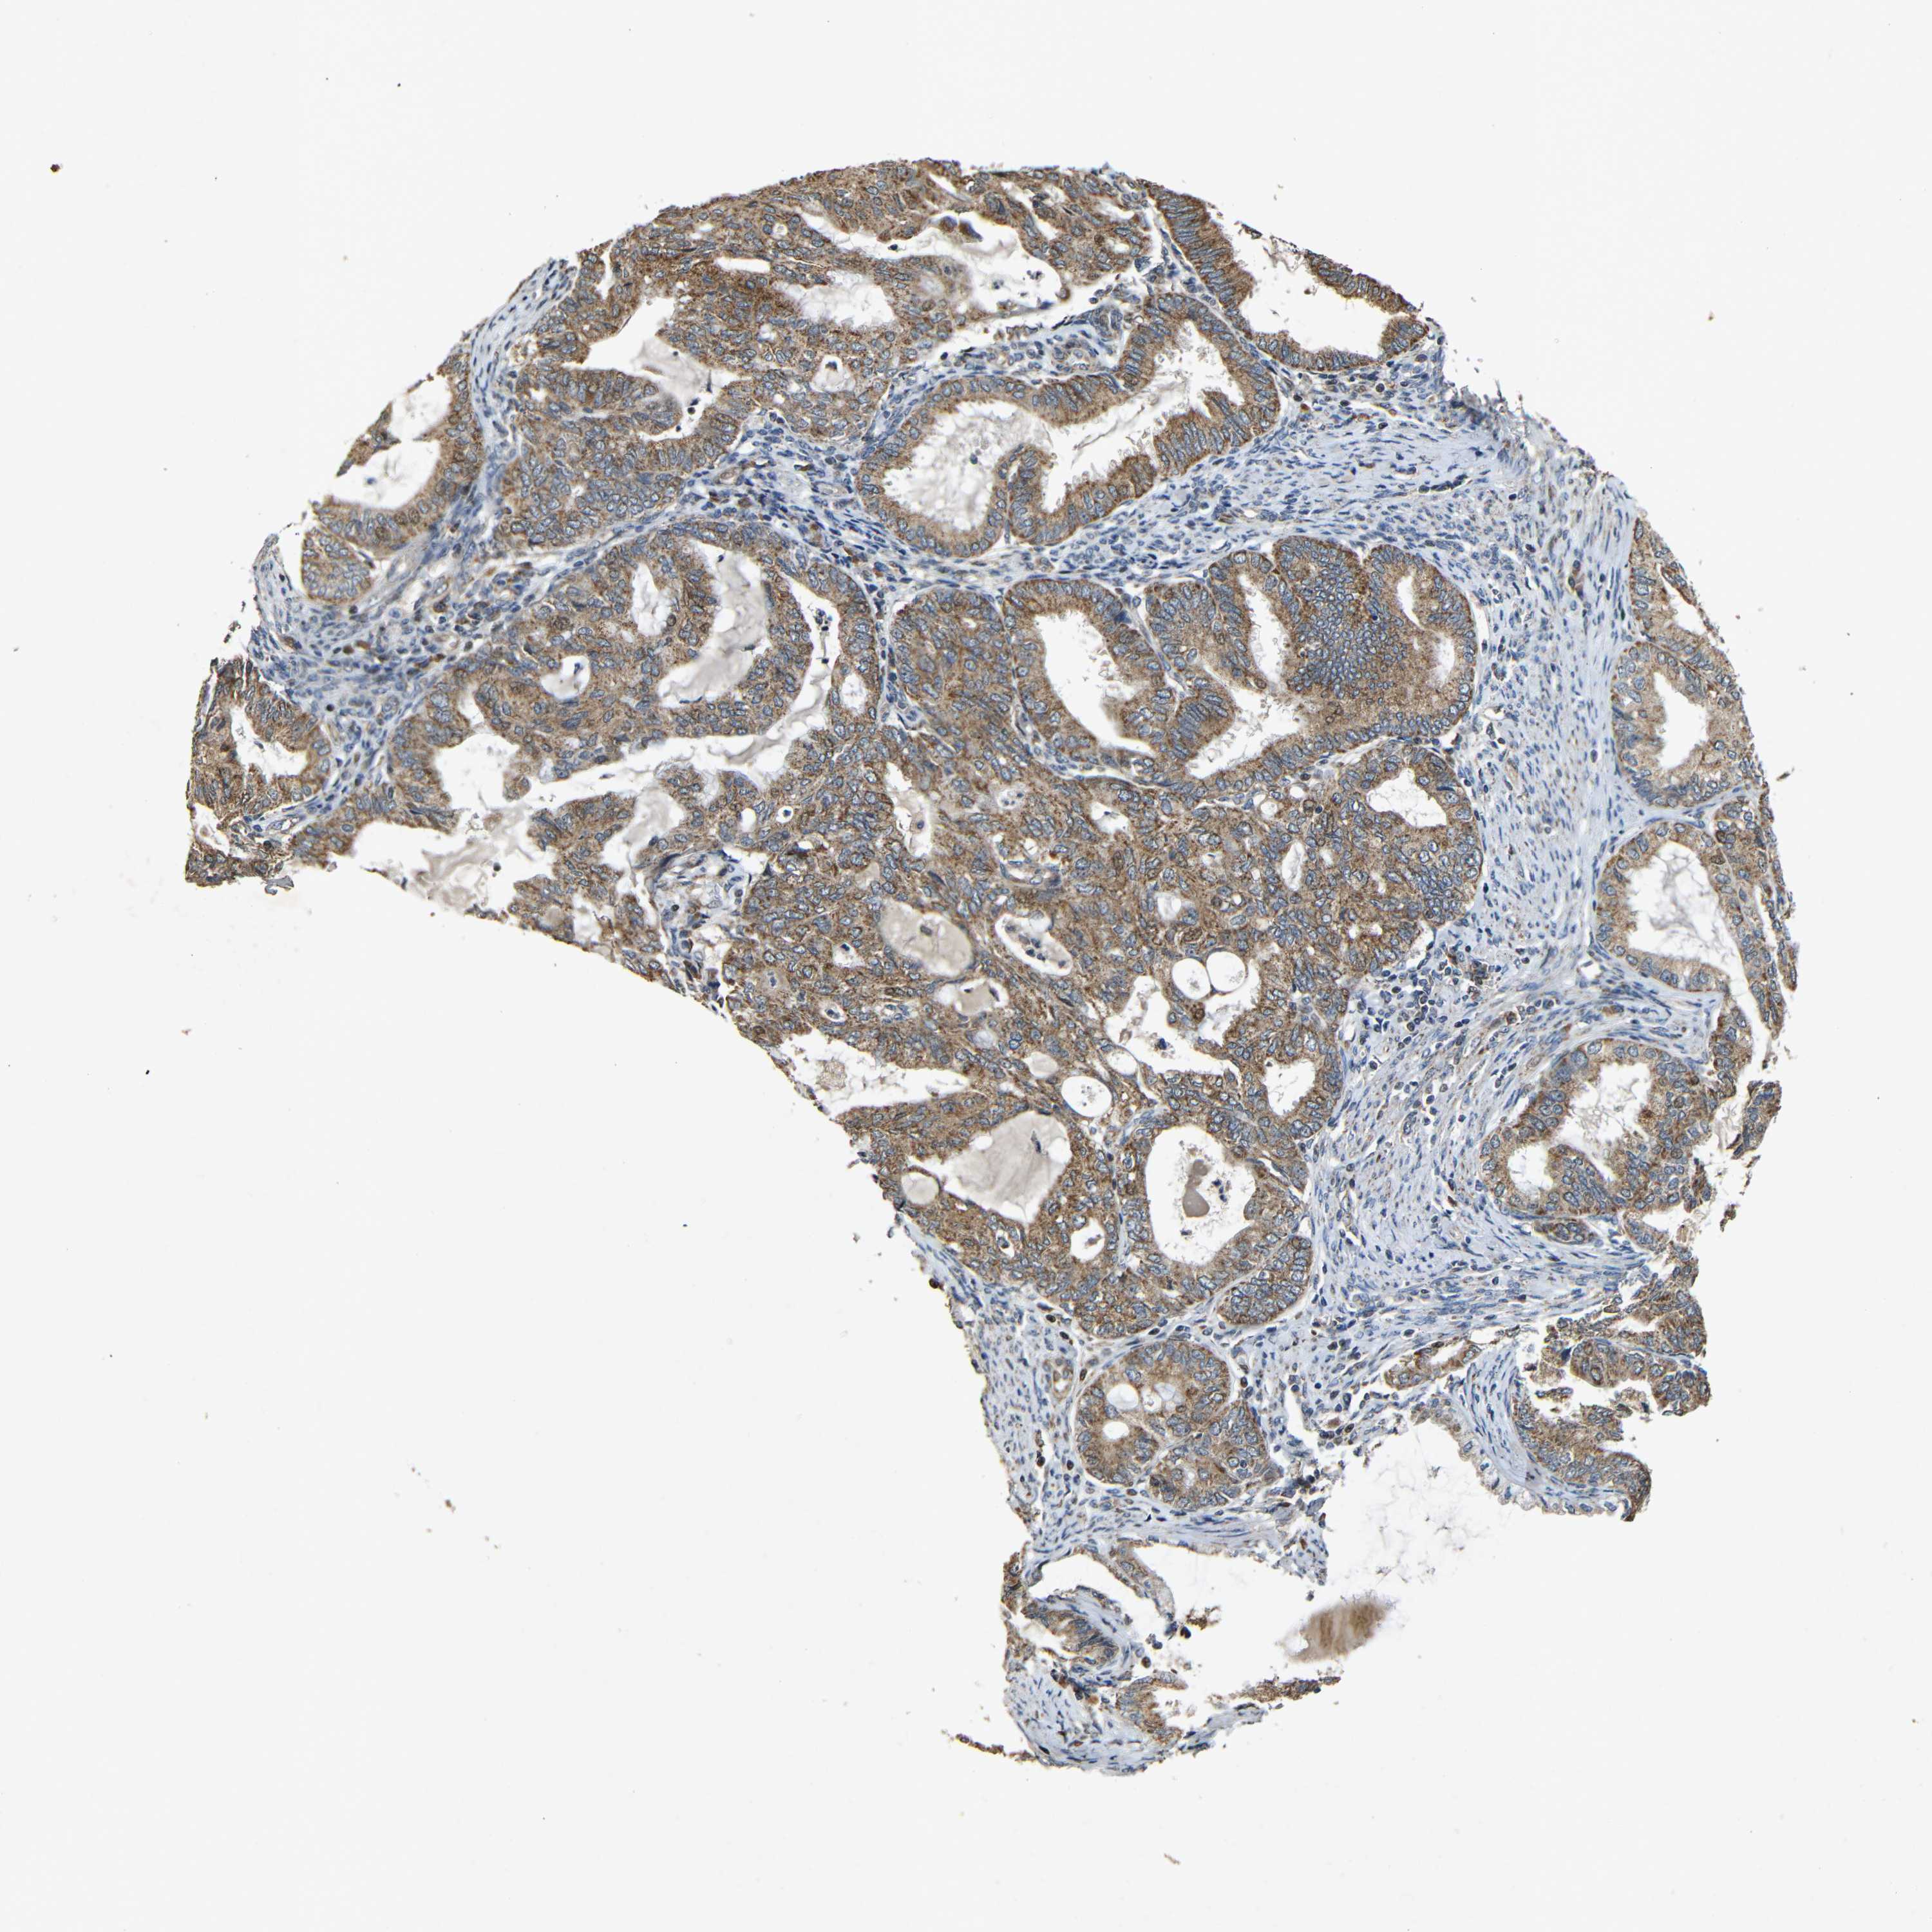

ENDOMETRIAL CANCER - Protein expressioni

A mouse-over function shows sample information and annotation data. Click on an image to view it in a full screen mode. Samples can be filtered based on level of antibody staining by selecting one or several of the following categories: high, medium, low and not detected. The assay and annotation is described here.

Note that samples used for immunohistochemistry by the Human Protein Atlas do not correspond to samples in the TCGA dataset.

Antibody stainingi

Antibody staining in the annotated cell types in the current human tissue is reported as not detected, low, medium, or high, based on conventional immunohistochemistry profiling in selected tissues. This score is based on the combination of the staining intensity and fraction of stained cells.

Each image is clickable and will lead to virtual microscopy that enables deeper exploration of all samples and also displays staining intensity scores, fraction scores and subcellular localization as well as patient and tissue information for each sample.

Antibody HPA011800

Staining

High

Medium

Low

Not detected

Intensity

Strong

Moderate

Weak

Negative

Quantity

>75%

75%-25%

<25%

None

Location

Nuclear

Cytoplasmic/membranous

Cytoplasmic/membranous,nuclear

Adenocarcinoma, NOS